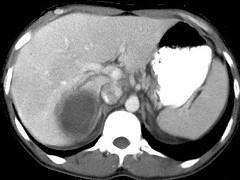

问题 女,25岁,上腹疼痛不适,低热,有阿米巴痢疾病史,CT检查发现肝右叶低密度病变,如图,最可能的诊断是 ( )

选项 A.原发性肝癌 B.肝血管瘤 C.肝错构瘤 D.阿米巴肝脓肿 E.肝转移瘤

答案 D